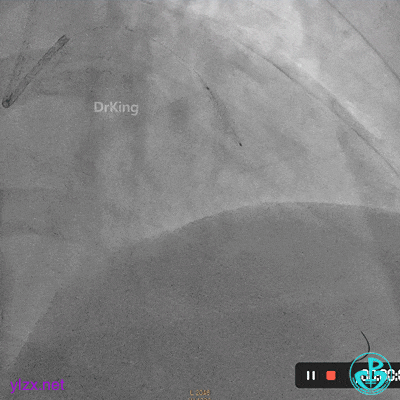

08 1个月后复查

RCA粗大全程瘤样扩张明显,自近段闭塞,TIMI血流0级;可见自身桥侧支逆供RCA远段。

LM未见明显狭窄,LAD开口至近段明显瘤样扩张,自近段闭塞,TIMI血流0级,D1瘤样扩张,TIMI血流2级;可见D1逆供LAD中远段及RCA中远段。

LCX发育小,内膜不光滑,TIMI血流3-级,逆供RCA中远段。